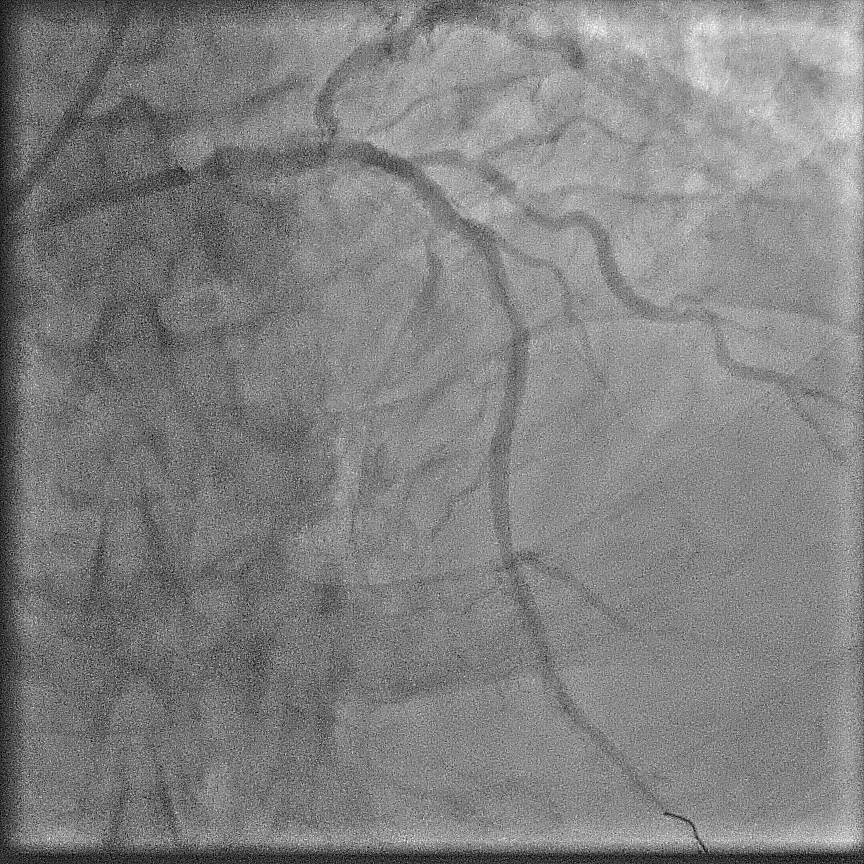

Angiography showed extensive calcification in the left and right coronary arteries, with severe stenosis at the left main ostium, severe in-stent restenosis at mid LAD, and severe, tortuous stenosis at the ostium and proximal LCx. The RCA was severely diffuse diseased with heavy calcification. The SYNTAX score was 58; BCIS CHIP score 7/13 - a very high risk and complex anatomy for PCI. STS surgery score risk for mortality was 3%; mortality and morbidity 18%.

The case was referred to cardiac surgeon. Due to extensive calcification of the aorta, surgery was deemed highly challenging. With surgery declined, a staged procedure of PCI and transcatheter aortic valve replacement (TAVR) was planned. Throughout, contrast use was minimized to reduce renal injury.First Procedure: Initial PCI targeted the left coronary system. Pre-dilation was performed at left main ostium, followed by at the most obstructive lesion in the LCx to reduce the risk of ischemia in subsequent interventions. The mid-LAD was treated with a drug-eluting balloon (DEB), followed by the LCx with DEB. Finally, the left main ostium was stented with a drug-eluting stent (DES), achieving a favourable outcome. Total contrast volume used was 28 mL.Second Procedure: The next day, PCI was performed on the RCA. Despite the challenging ostial lesion, positioning of the guiding catheter (AL1) was successful. Balloon pre-dilation and placement of two DESs in the proximal RCA achieved satisfactory result. Total contrast used was 31 mL. The patient experienced significant relief from angina following these interventions.One Month Later: TAVR was performed using an Evolut Pro+. Due to severe iliofemoral and aortic calcifications, device delivery was challenging. TAVR was ultimately succesful; peak aortic valve gradient was decreased from 50 mmHg to no residual gradient.